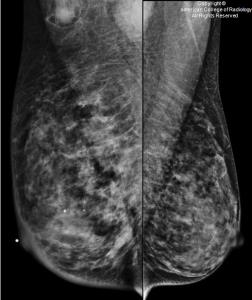

Direct breast density consults with radiologists empower patients to make informed decisions about their breast health.

Read case study »